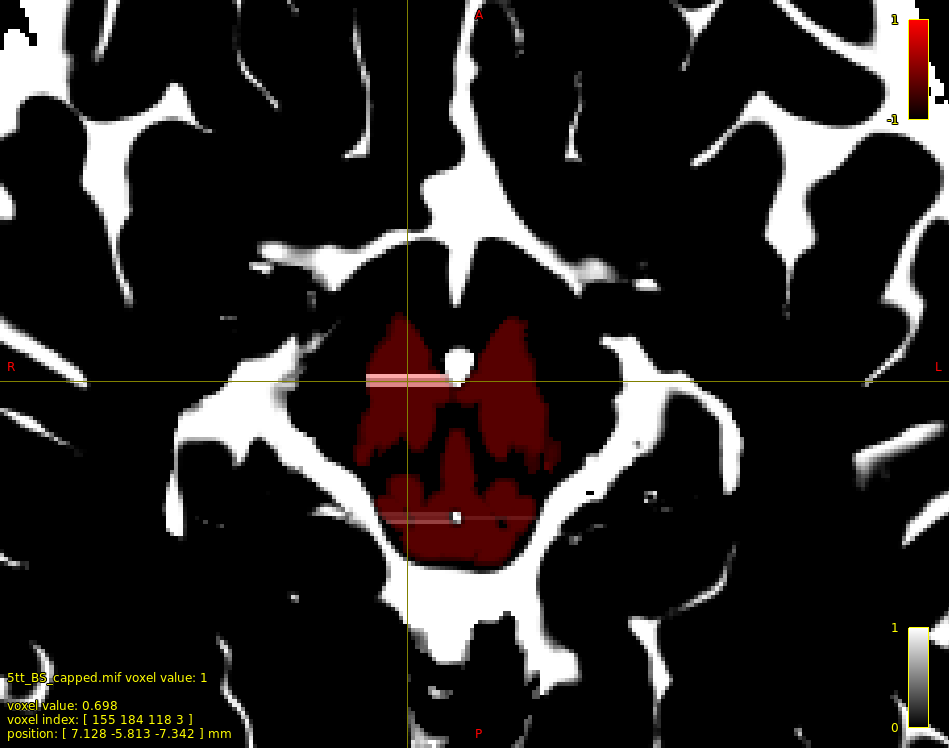

5ttedit: Support for floating-point input images #2558

That's a particularly unusual effect given that the command operates entirely independently on each voxel. @Arshiyasan any chance of sharing some data so that I can attempt to reproduce? |

Interesting... Reading the fix, I can't quite understand what the reason for those strange bands was. Did you find out what was causing that pattern? |

That was me failing to always move the thread-specific position in the input image before reading from it; therefore sometimes it would be reading input image data from a previously-processed voxel. |

@Arshiyasan Feel free to give a try if you'd like; might be preferable to thresholding at 0.5.

(currently a zero in an input image means don't make any modification)